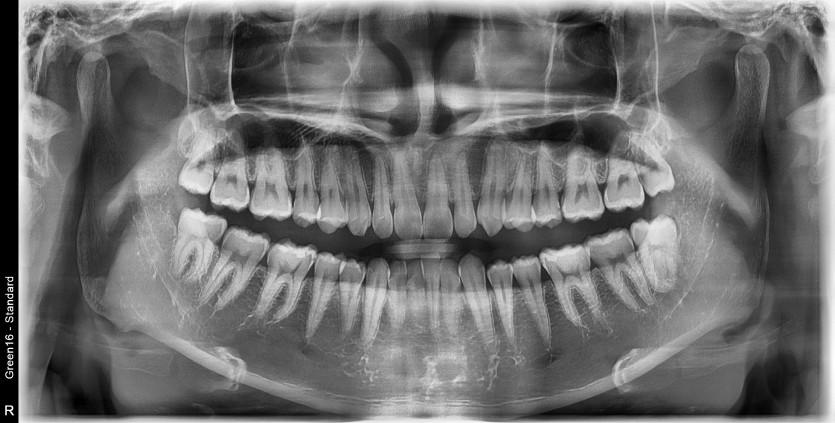

#28,38 사랑니 발치

구강 외과 전문의가 당일 발치했습니다.